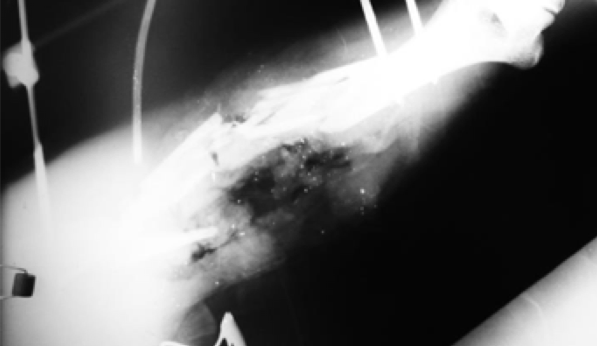

Esta formação do neck é um fator de grande importância nos calibres de alta velocidade, entretanto não é o único a produzir danos. Quando um projétil de alta velocidade atinge um osso, a grande fragmentação tanto do osso quanto do projétil aliada à velocidade que tais fragmentos serão impulsionados aumenta consideravelmente a gravidade da lesão, resultando nos “danos terciários”. Quando um ou mais ossos dos membros são atingidos, a laceração tecidual pode ser tão ampla a ponto de praticamente resultar em uma amputação traumática do membro, que ficará preso ao corpo tão somente por retalhos de pele e músculos, como mostrado na figura seguinte: